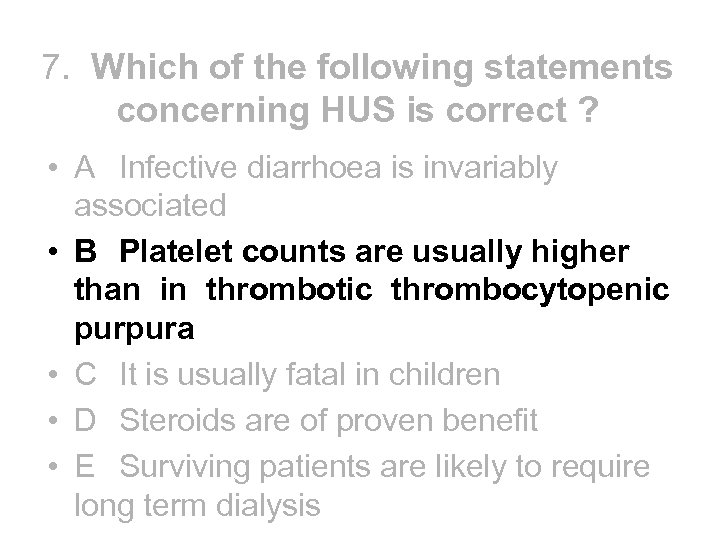

7. Which of the following statements concerning HUS is correct ? • A Infective diarrhoea is invariably associated • B Platelet counts are usually higher than in thrombotic thrombocytopaenic purpura • C It is usually fatal in children • D Steroids are of proven benefit • E Surviving patients are likely to require long term dialysis

7. Which of the following statements concerning HUS is correct ? • A Infective diarrhoea is invariably associated • B Platelet counts are usually higher than in thrombotic thrombocytopaenic purpura • C It is usually fatal in children • D Steroids are of proven benefit • E Surviving patients are likely to require long term dialysis

7. Which of the following statements concerning HUS is correct ? • A Infective diarrhoea is invariably associated • B Platelet counts are usually higher than in thrombotic thrombocytopenic purpura • C It is usually fatal in children • D Steroids are of proven benefit • E Surviving patients are likely to require long term dialysis

7. Which of the following statements concerning HUS is correct ? • A Infective diarrhoea is invariably associated • B Platelet counts are usually higher than in thrombotic thrombocytopenic purpura • C It is usually fatal in children • D Steroids are of proven benefit • E Surviving patients are likely to require long term dialysis